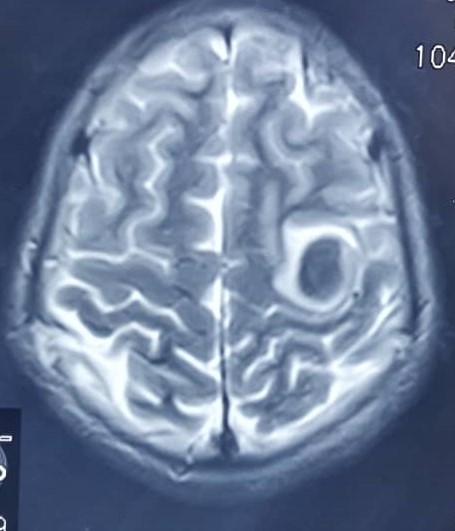

Neuroimaging studies were also done: Brain MRI, which reported a well-defined, rounded, T1 heterogeneous, (central core of iso intensity to grey matter with a rim of hyperintensity), collection measuring (2.5TR x 2.5AP x 2.5CC) cm in the left parietal lobe (Figure 1). This collection ‘blooms’ on T2/ SWI imaging by suggesting early subacute haemorrhage (Figure 2). There was surrounding vasogenic oedema, No enhancement was seen post-gadolinium administration and does not ‘restrict’ on DWI/ADC imaging. On a complementary Brain CT Scan done 2 days later was described as a hyperdense collection (mean attenuation of 58HU) in the left parietal lobe with minimal surrounding oedema. No significant mass effect or shift of midline structures is seen. Findings in-keeping with early left parietal lobe subacute haemorrhage (Figure 3).

Figure 2 Brain MRI T2-Left parietal lobe collection “blooms” in T2.